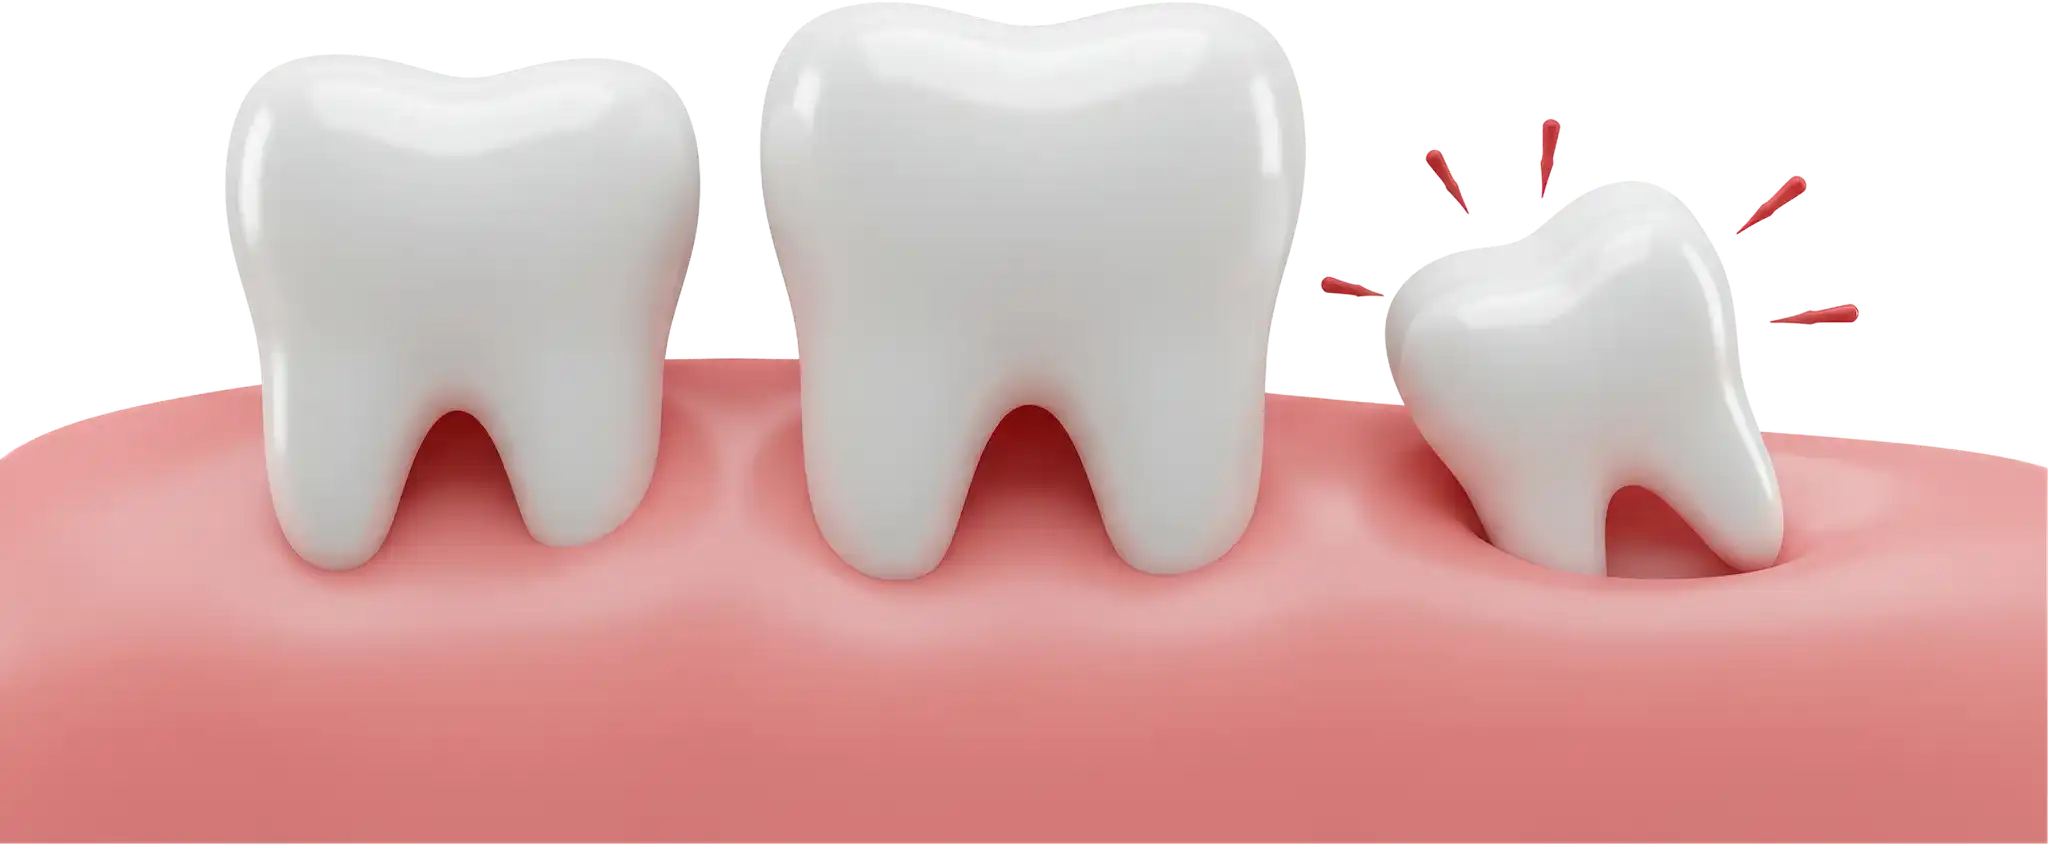

When wisdom teeth come in sideways, they push hard against your second molars. This pressure can crack or damage these healthy teeth, which might then need expensive repairs or even removal themselves. By getting a preventive wisdom tooth removal, we save your adjacent teeth from harm and prevent a whole string of future dental problems.

As wisdom teeth grow, the pressure they create can shift and crowd all your other teeth. This pressure can sometimes undo the hard work of previous orthodontic treatment (like braces or clear aligners). If you’ve invested in a straight smile, preventive wisdom tooth removal is a smart way to protect that investment and keep your alignment perfect.